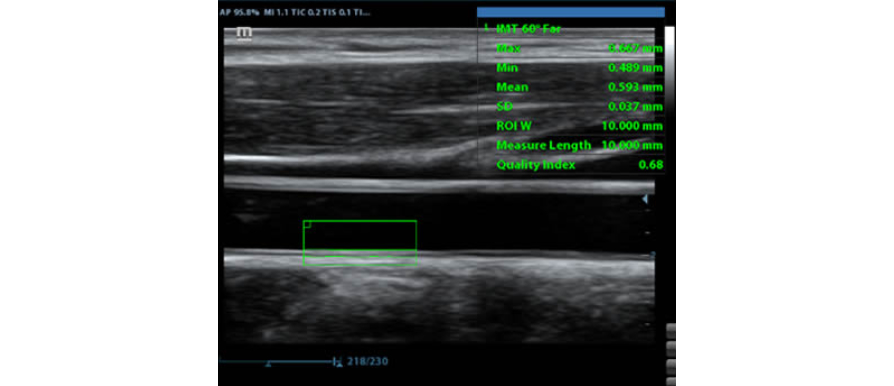

IMT (grosor Ăntima-media)

MediciĂłn automĂĄtica del grosor de la pared anterior y posterior, lo que proporciona un indicador preciso del estado de la carĂłtida.